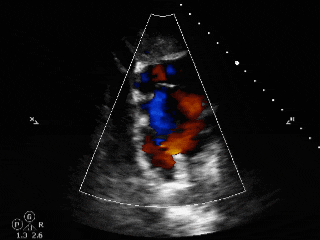

释放后评估

封堵器位置正确、形态良好

彩色多普勒血流成像显示无残余分流存在

封堵成功